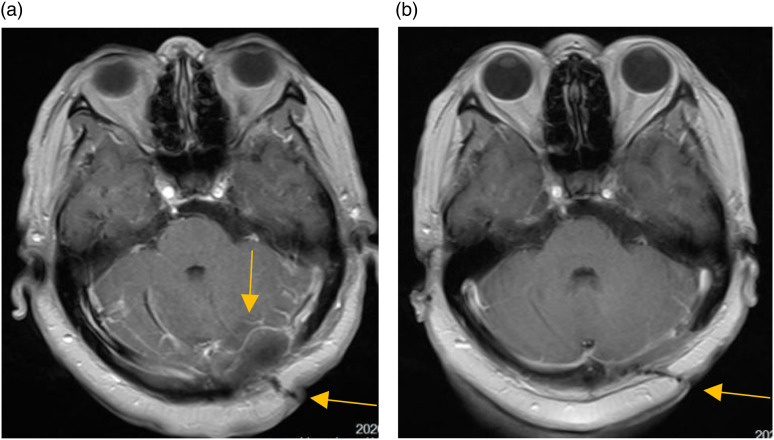

Osteosarcomas predominantly manifest in the long bones of the extremities, with rare occurrences in the skull. A case involving of a 53-year-old female who presented to the authors' hospital for examination due to dizziness was incidentally found to have an occipital bone mass, which was initially diagnosed as a benign tumor and did not receive sufficient attention. Two years later, owing to tumor enlargement, the patient underwent further evaluation at the same institution, which revealed evidence of occipital bone destruction. Pathological analysis confirmed the diagnosis of osteosarcoma. The patient underwent surgical resection followed by radiotherapy. Despite its infrequency and uncharacteristic initial presentation, skull osteosarcomas should not be overlooked.